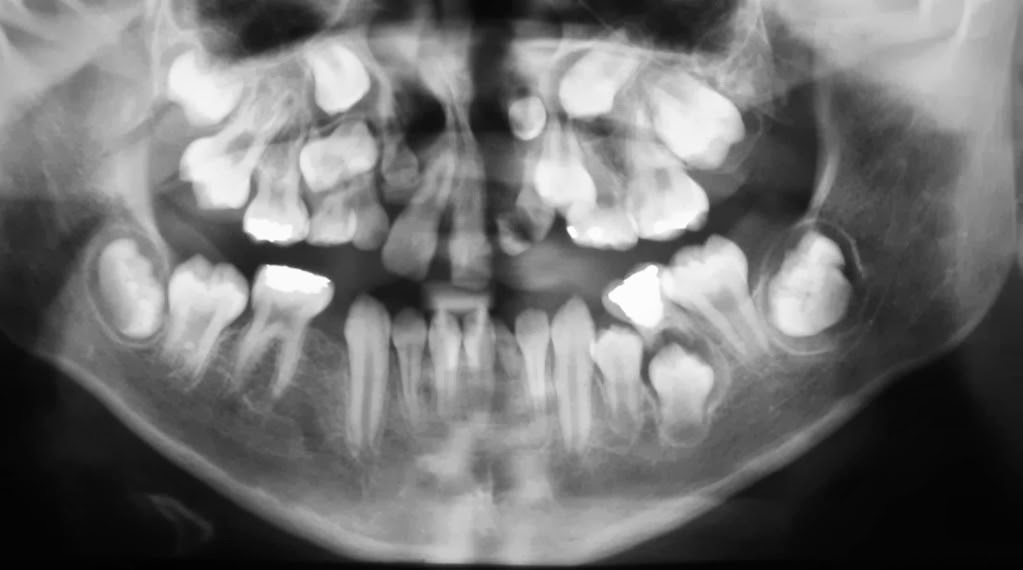

Opacidades Pulpares o Calcificaciones

Agrandamiento Pulpar

Es una anomalía dentaria, puede estar asociada a enfermedades metabólicas.

Obliteración Pulpar

Posibles causas: edad, dentinogénesis imperfecta y corticoesteroides.

Hipercementosis

Resorción Interna

Causas sugeridas: Procesos inflamatorios, perdida de vitalidad del cemento, cambios vasculares en la pulpa, canales radiculares accesorios y traumatismos.

Resorción Externa

Causas sugeridas: Inflamación periapical, reimplantación dentaria, tumores o quistes, fuerzas excesivas e impactación dentaria.

Periodontitis Aguda Apical

Es una respuesta inflamatoria del ligamento periodontal totalmente sintomático.

Absceso Agudo Apical

Puede ser causado por muerte pulpar, trauma, irritación mecánica o irritación química.

Periodontitis Crónica Apical

Causas sugeridas: granuloma apical, quiste apical, absceso apical o absceso recurrente.

Granuloma apical

Quiste Apical

Absceso Cónico Apical

Quiste Residual

Cicatriz Apical

Es de tamaño constante, de menor tamaño que el quiste y tarda de 1 a 10 años para regresión.

Absceso Recurrente

Lesión preexistente asintomática.

Osteítis Condensante Apical

Inflamación leve con aumento de la densidad del hueso periapical.

Osteoesclerosis

Aumento de formación ósea.